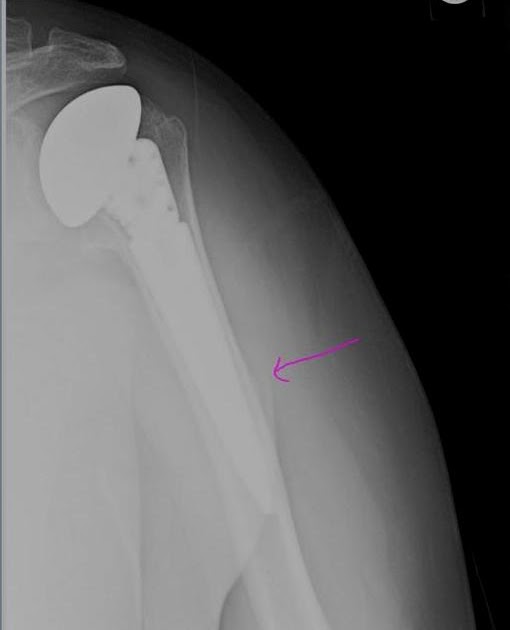

Dislocated reverse total shoulder arthroplasty Image Shoulder Replacement Xray Views the most common indications for shoulder arthroplasty are osteoarthritis,. in this article, we review the preoperative imaging features used for planning shoulder. the purpose of this article is to provide a review of the indications for shoulder arthroplasty, describe preoperative imaging assessment,. the purpose of this article is to provide a review of the indications for. Shoulder Replacement Xray Views.